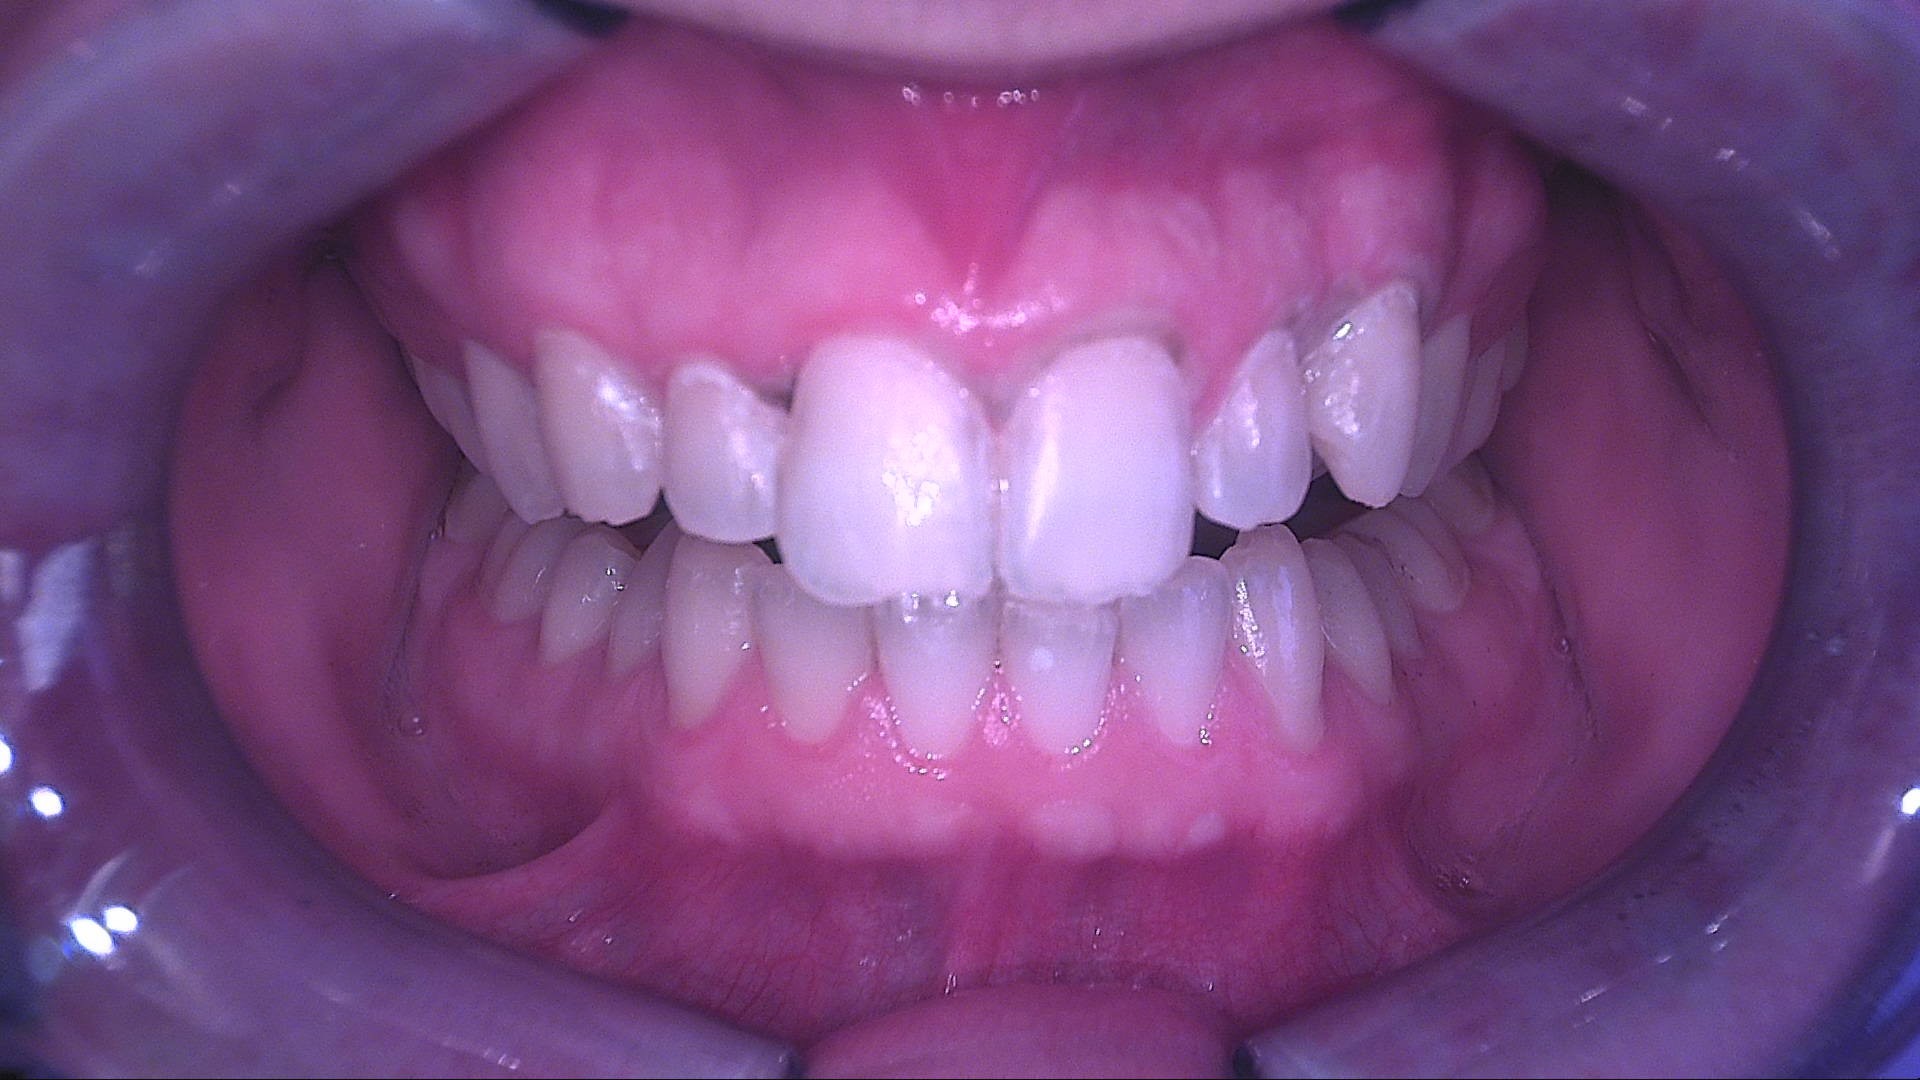

Il paziente è stato richiamato a un mese per la rivalutazione. La situazione clinica risulta stabile: le aree precedentemente opache mantengono un aspetto più uniforme e meno evidente.

La nuova acquisizione con QrayCam Pro mostra valori ΔF compresi tra –6,2% e –8,5% e una ulteriore riduzione dell’area di white spot a meno di 200 px², a conferma di una stabilizzazione del risultato.

Fig. 5A - Controllo a un mese in luce bianca: mantenimento dell'uniformità cromatica.